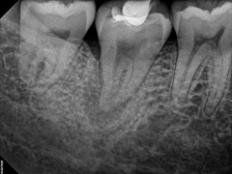

Apexogenesis

This procedure encourages the root to continue development as the pulp is healed. The exposed pulpal tissue is covered with MTA. This will allow for the exposed tissue to heal against the MTA, keeping the pulpal tissues vital and encouraging further maturation and growth of the tooth. This process will enable the tip of the root (apex) to continue to close as the child gets older. In turn, the walls of the root canal will thicken, and the tooth will become stronger. If the pulp heals, no additional treatment will be necessary. The more mature the root becomes, the better the chance for the survival of maturing.